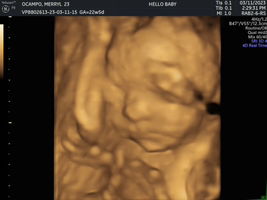

kakaultrasound ko lang din 22w and 5days nagpakita agad π₯° Yung mukha nga lang nya ayaw ipakita